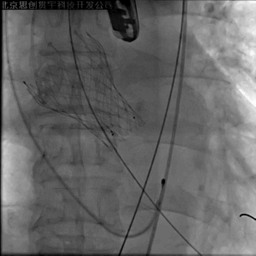

应用PLUS回收支架,重新定位

释放后造影见中度瓣周漏,彩超提示支架没有充分打开

22mm球囊后扩